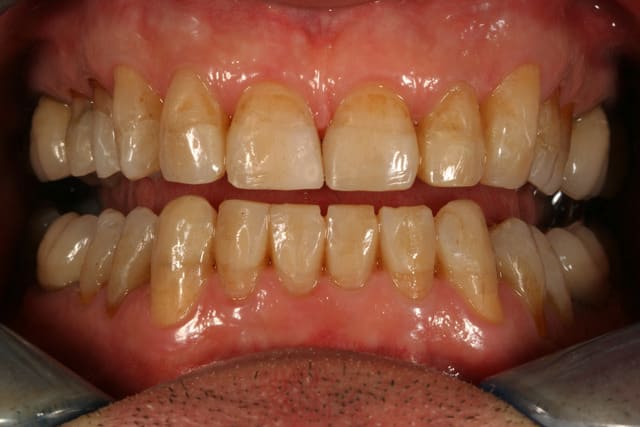

j'en profite pour mettre à jour le cas

j'ai enfin fait la gouttière ... pour diverses raisons, ça a trainé 4 bons mois, mais c'est fait

il a eu le temps de casser un angle d'une centrale, une cuspide palatine d'une prémo, mais rien n'a été décollé

j'ai pu réparer la centrale facilement avec le même compo que celui utilisé pour faire les onlays

on a eu une petite discussion sur brossage, il devait être habitué à ses dents très courtes, mais du coup il brossait pas jusqu'à la gencive, il y avait un gros paquet de plaque à ces endroits, par contre il passe bien les brossettes.

je ferais un polissage dans quelques mois, et puis régulièrement après ça (à priori entre une et deux fois par an, en maintenance)

il est très content, n'a pas d'envie particulière pour des facettes en plus (et tant mieux, j'aurais plus peur avec de la céramique qu'avec le compo facile à réparer)

j'ai complètement oublié de lui proposer un éclaircissement (même gratos)